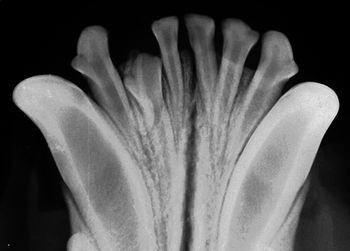

Visual examination, anesthetized probing and intraoral radiography can help veterinarians assess each patient's level of disease.

Visual examination, anesthetized probing and intraoral radiography can help you assess each patient’s level of disease.

According to industry estimates, less than 10 percent of small animal practices have dental radiograph units and of those, less than 10 percent take intraoral films on every dental case.